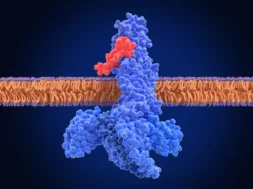

Άλλες ορμονικές αλλαγές μπορεί να σας οδηγήσουν να αναπτύξετε ένα άλλο κοινό σύμπτωμα, την γαστροοισοφαγική παλινδρόμηση. Τα επίπεδα της ορμόνης προγεστερόνης, για παράδειγμα, αυξάνονται σταθερά κατά τη διάρκεια της εγκυμοσύνης. Αυτό μπορεί να οδηγήσει τον οισοφαγικό σφιγκτήρα μυ –που βρίσκεται στο κάτω άκρο του οισοφάγου, πριν συναντήσει το στομάχι- να γίνει πιο χαλαρός. Η χαλάρωση αυτού του μυός διευκολύνει το οξύ του στομάχου να πάει στον οισοφάγο. Αυτό μπορεί να προκαλέσει επώδυνη αίσθηση καψίματος στο πάνω μέρος της κοιλιάς σας ή ακριβώς πίσω από το στέρνο.